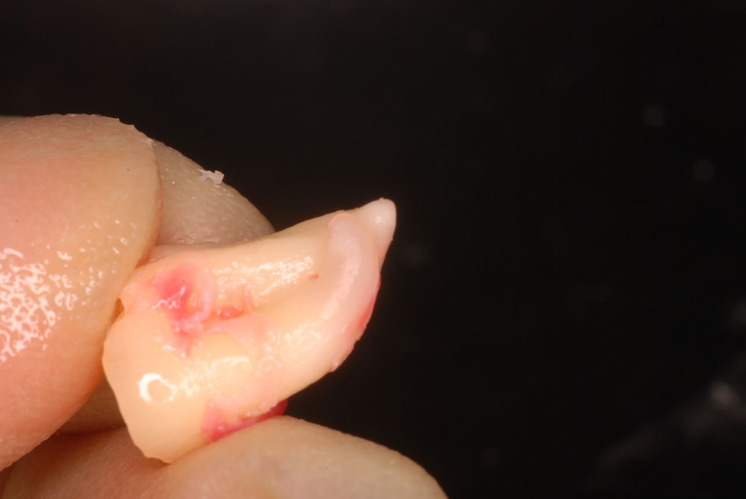

外したところです。中は虫歯のオンパレードでした。

適合が悪い銀歯が装着されていて更に虫歯の取残しにより歯髄炎症を起こして神経を取らざるをえなくなりました。神経を除去すれば痛みはなくなります。でもそれは死ぬことなのです。ほぼ寿命は半減したと考えるしかないのです。